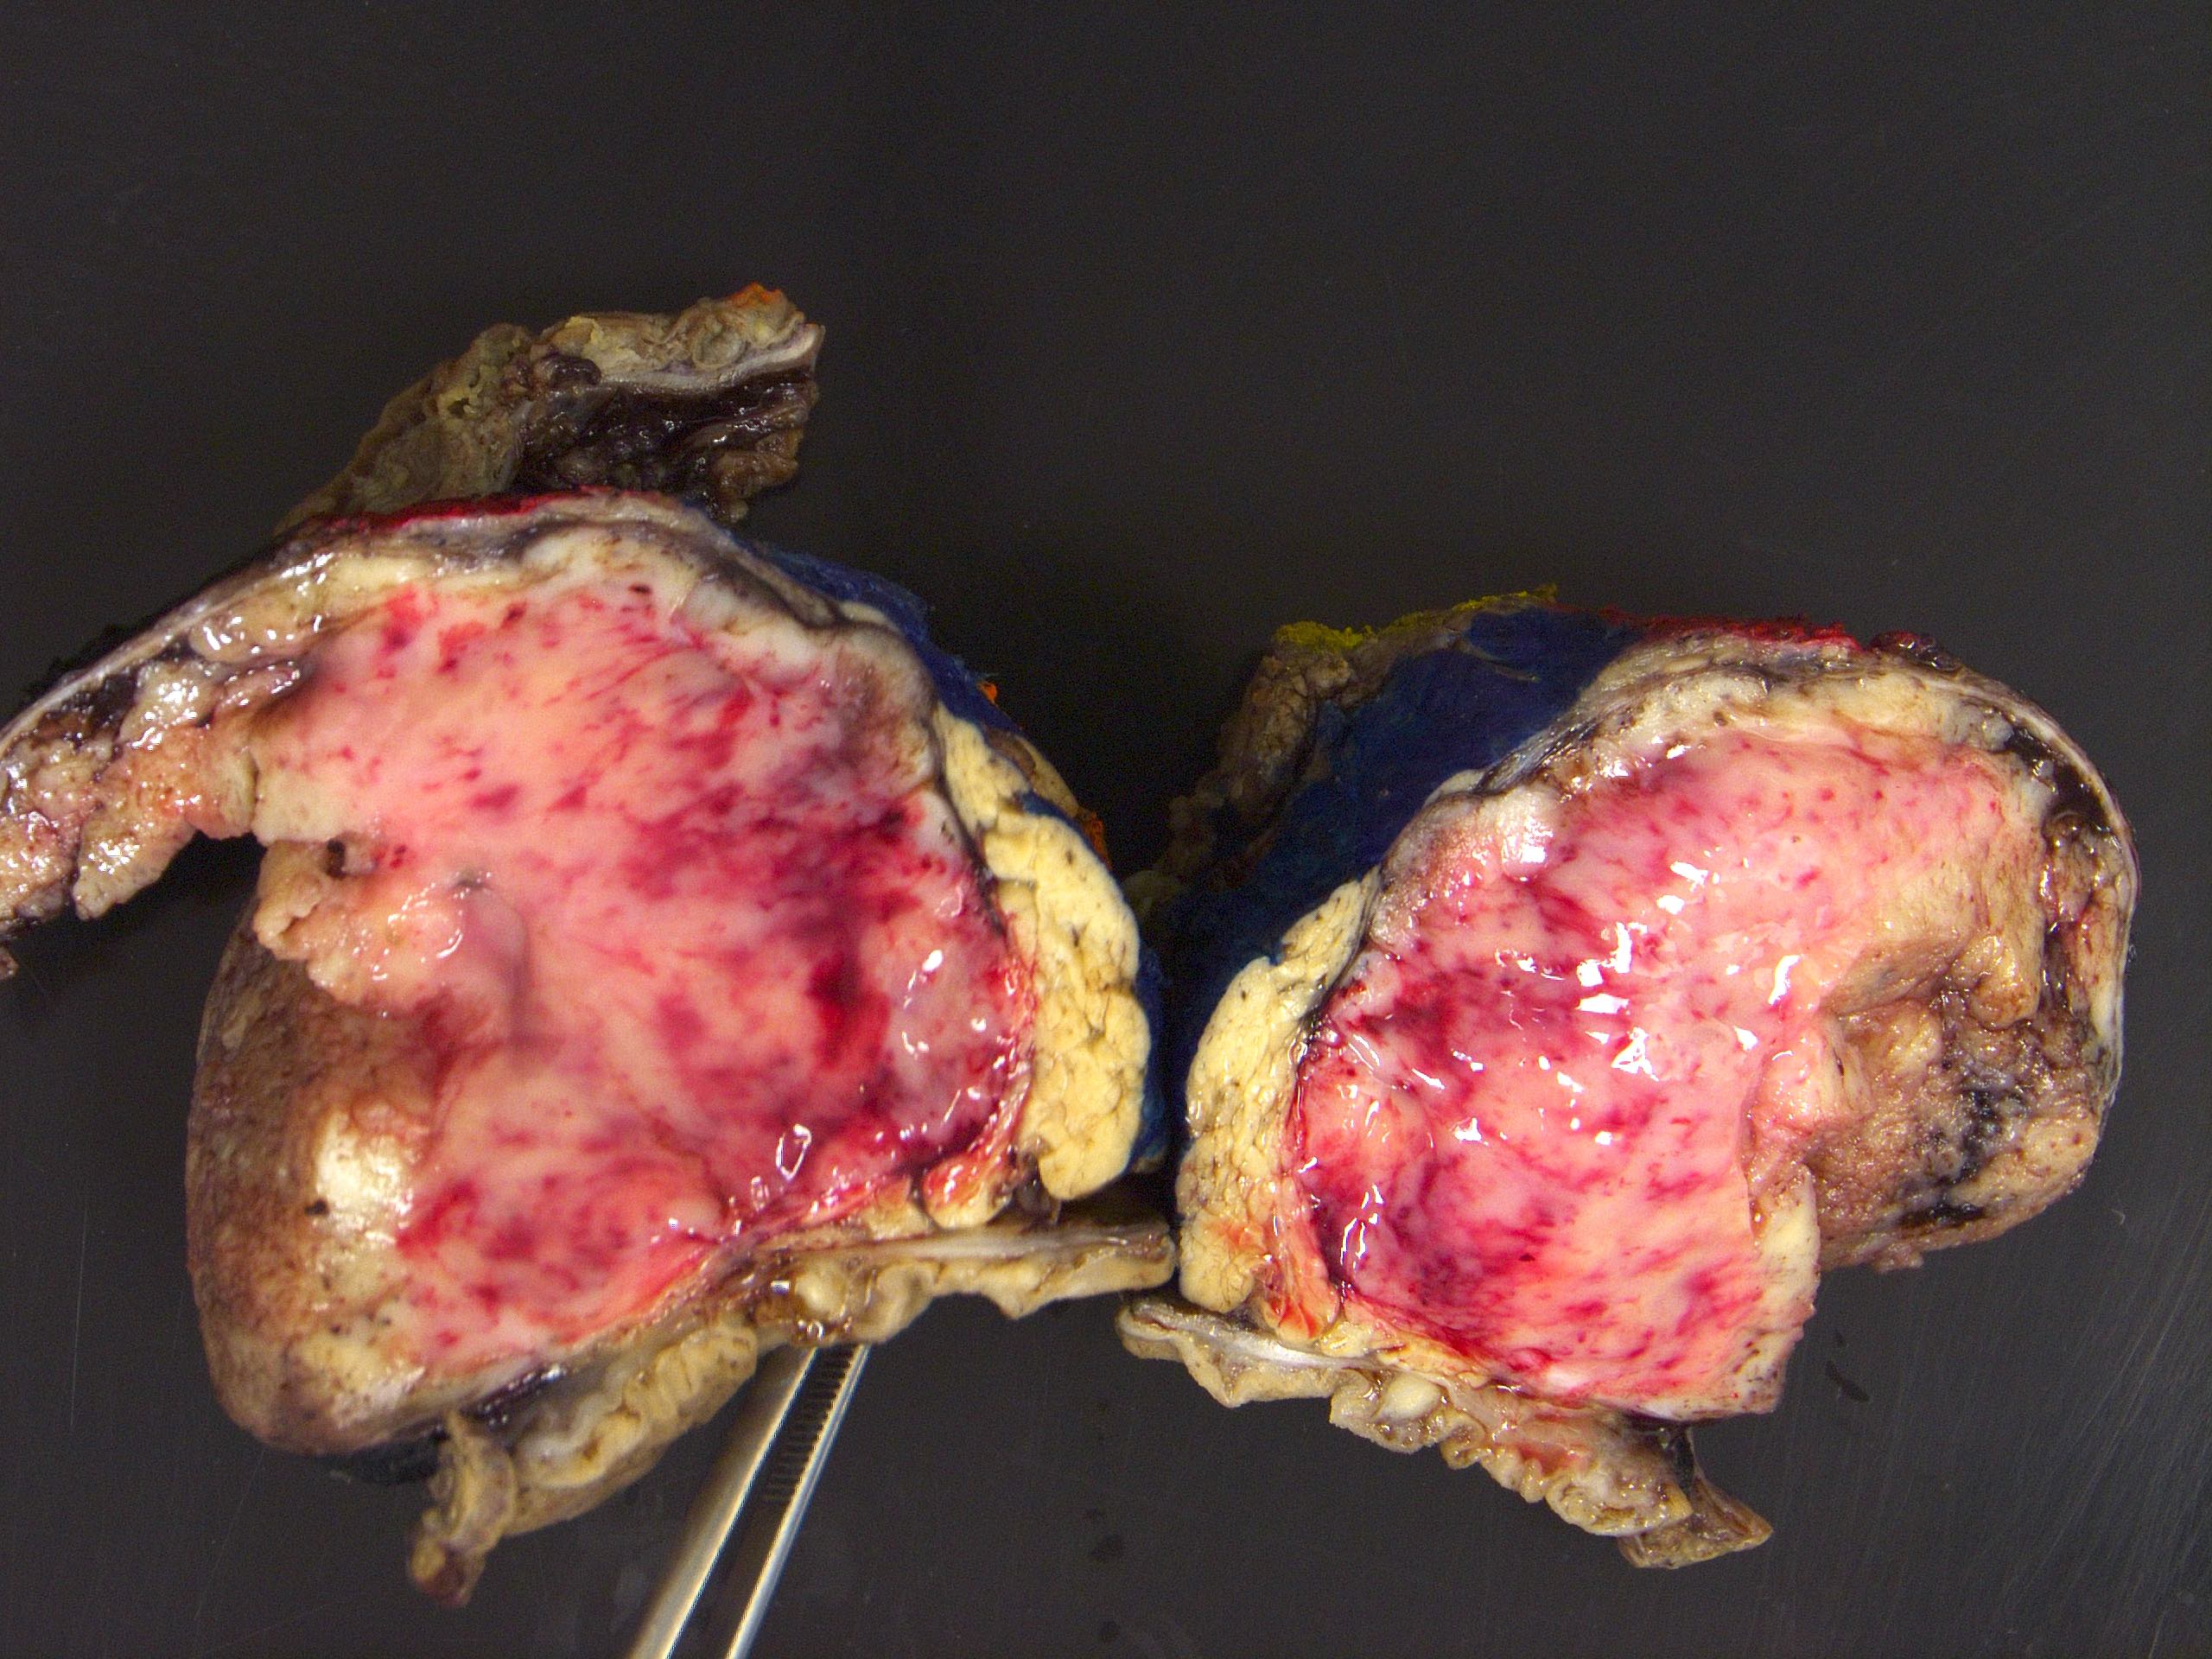

Gross description

- Range from 0.5 to 34.5 cm, with a mean diameter of 6 cm

- Well defined, encapsulated, with variable amount of solid and cystic patterns

- Smaller lesions tend to be more solid but less sharply circumscribed

- Larger tumors demonstrate a fibrous pseudocapsule and have a variegated and friable cut surface

- Cystic degeneration and hemorrhage are common findings in larger specimens

- Rarely, may extend into adjacent structures, such as duodenum

- Reference: Arch Pathol Lab Med 2020;144:829

Gross images

Contributed by Omid Savari, M.D., Dr. Andreas Schulz, Manfred Stolte, M.D., Dr. Helmut Luchtrath, Wei Chen, M.D., Ph.D., Nakul Anush Ravish, M.B.B.S. and Case #121